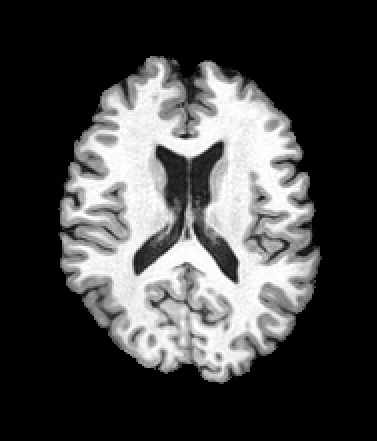

A trained MetaVoxel model can be unconditionally sampled by drawing Gaussian or categorical noise for each variable at timestep , and iteratively apply the denoising network until reaching . Unlike conventional diffusion models that focus solely on image generation, MetaVoxel can generate coherent synthetic patient profiles from the joint distribution , as shown in Figure 2.

A distinctive strength of MetaVoxel is its ability to perform flexible zero-shot inference for a broad spectrum of tasks with arbitrary subsets of inputs. To enable this, we reinterpret the RePaint strategy described in Section 2: just as RePaint performs conditional image generation by specifying a binary mask that marks which pixels are fixed, we can further designate any subset of MetaVoxel’s variables as “known” conditions. At each denoising step, these known variables are overwritten with their re-noised values, ensuring that they remain fixed throughout the sampling trajectory, while the remaining variables evolve according to the learned reverse process. This keeps the synthesized variables consistent with the conditioning, analogous to how RePaint produces inpainted regions consistent with the known region. Although MetaVoxel learns the joint distribution , different downstream tasks can be realized simply by choosing which variables to fix during sampling. Image inpainting is achieved by fixing pixel regions of the image variable***see examples in Appendix (Figure B.2); conditional image generation by fixing variables such as age or sex; regression tasks (e.g., age estimation) by fixing any combination of image and sex; and classification tasks (e.g., sex prediction) by fixing any combination of image and age. As more variables are included in the joint model, the range of possible zero-shot tasks naturally expands. For example, when multiple imaging modalities are present, fixing one modality and sampling the other enables image-to-image translation.